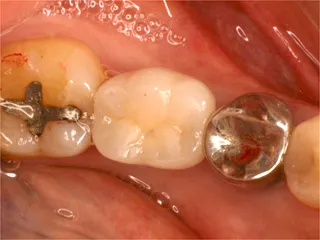

| 自費治療 インプラント |

治療前

インプラントは第二の歯とも呼ばれ 顎の骨に金属製のネジを立てて 人工の歯を取付けます 当院では高い技術と経験で対応しています ■長所 ・しっかり噛むことができる ■短所 ・禁忌症がある ・高い インプラント・くわしく |